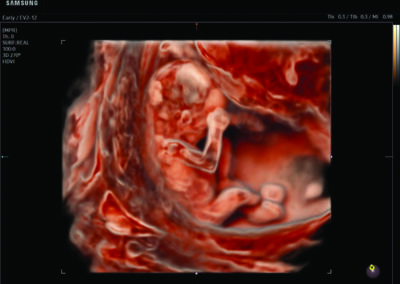

Comprehensive, advanced and expert MFM care for high-risk pregnancies

- Fetal anomalies